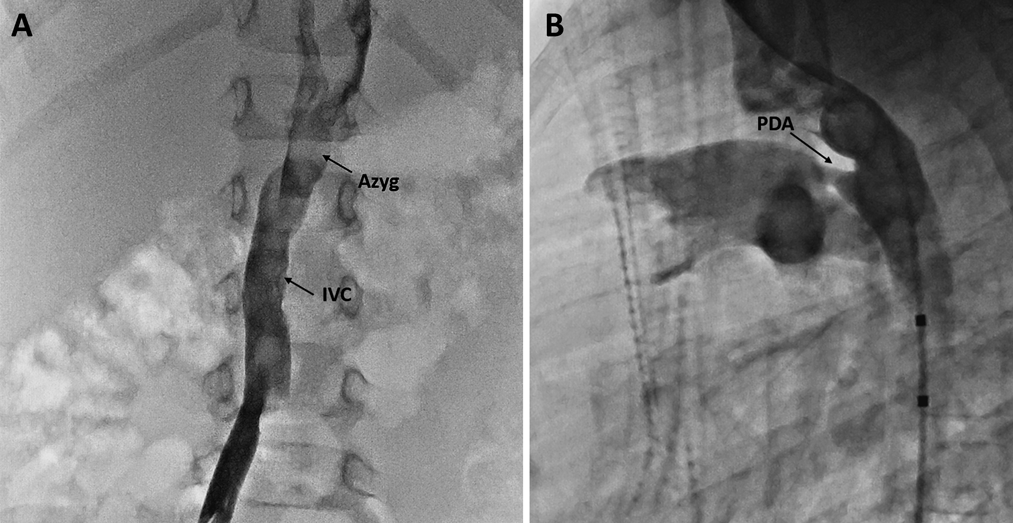

A 2 year-old (12 kg) female with an interrupted IVC with azygous continuation to the right superior vena cava was referred for transcatheter closure of a moderate PDA associated with left heart dilation. At catheterization, her pulmonary artery pressures were normal and her Qp/Qs was 1.7. Angiography confirmed IVC interruption and a moderate type A PDA (Fig. 1). The PDA was 7.5 mm long, the pulmonary artery end of the PDA measured 2 mm, and the aortic end measured 4.5 mm. The patient had a left aortic arch with normal branching. The PDA was crossed antegrade from the RIJ with the wedge catheter. An Amplatzer extra stiff wire (AGA Medical Corporation, Golden Valley, MN) was used to advance a 6 F 180 degree Amplatzer Torqvue delivery sheath (AGA Medical Corporation, Golden Valley, MN) across the PDA and into the descending aorta. A 5–4 mm Amplatzer Duct Occluder (ADO) (AGA Medical Corporation, Golden Valley, MN) device was chosen for closure. The delivery cable associated with this device is stiff; in the setting of a tortuous approach from the RIJ, we were concerned that this stiff cable may not reliably unscrew to facilitate device release. Thus, we took the floppier delivery cable from an Amplatzer Vascular Plug II (AVP II) (AGA Medical Corporation, Golden Valley, MN) device and attached it to the ADO device. Using the Amplatzer delivery sheath, the 5–4 mm ADO was deployed (Fig. 2A) and released without issue. Following device release, the aortogram showed no residual ductal flow and no aortic obstruction (Fig. 2B). The patient is doing well 6 months after the procedure with echocardiogram showing no residual PDA flow and no aortic or left pulmonary artery obstruction.

Fig. 1 (A) AP view of inferior vena cava angiogram showing IVC interruption with continuation via the azygous vein. (B) Lateral review of an aortogram showing moderate, conical type A patent ductus arteriosus. Azyg, azygous vein; IVC, inferior vena cava; PDA, patent ductus arteriosus.